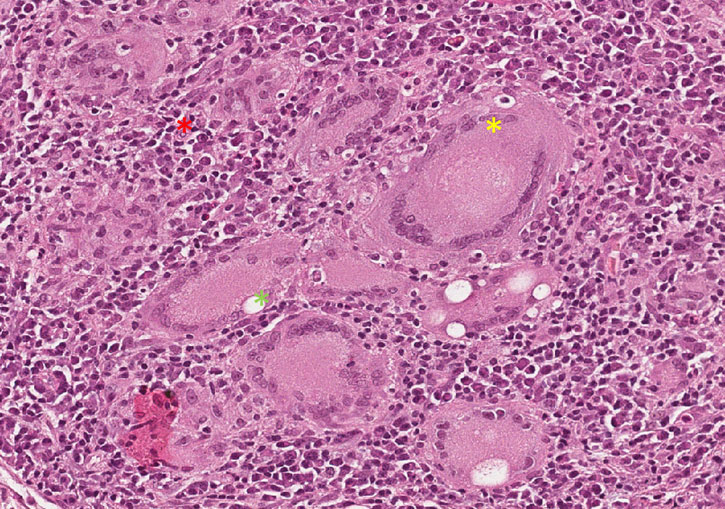

Fragmento de tecido pulmonar no qual parte da arquitetura alveolar é preservada enquanto em algumas regiões demonstram a formação de granulomas epitelióides caseosos. Na porção superior observa-se um granuloma extenso apresentando áreas de necrose caseosa central (material amorfo com perda de seletividade tintorial), entremeada por macrófagos epitelióides (núcleo claro e mais alongado, semelhante a morfologia de uma célula epitelial), linfócitos e células gigantes do tipo Langhans (asteriscos amarelos), circundadas por fibroplasia. Na porção dos alvéolos mais preservada também se nota a presença de um granuloma menor sem necrose central, mas apresentando os outros componentes.

Observar a formação dos granulomas compostos por macrófagos epitelióides, células gigantes do tipo Langhans (asteriscos amarelos), linfócitos (asteriscos verdes) e fibroplasia.